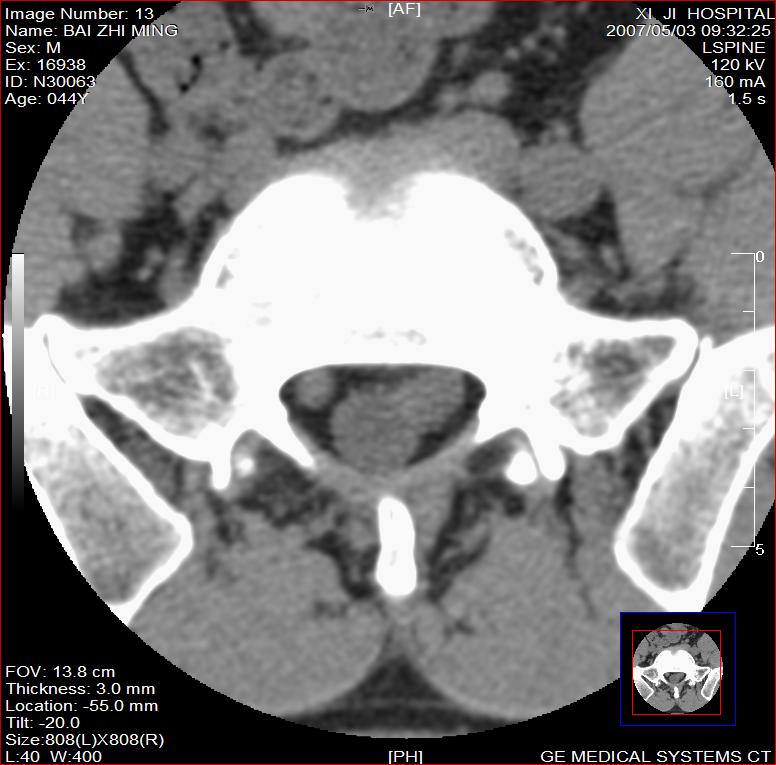

男,44岁,腰痛3月,加重3天。

同意2楼,左侧神经根增粗,欠规整,神经根炎或神经源性肿瘤可能,建议mri检查。

左侧神经根增大.并硬脊膜囊受压(1,神经根炎2神经根肿瘤)

左侧神经根增粗,欠规整,神经根炎或神经源性肿瘤可能,建议mri检查